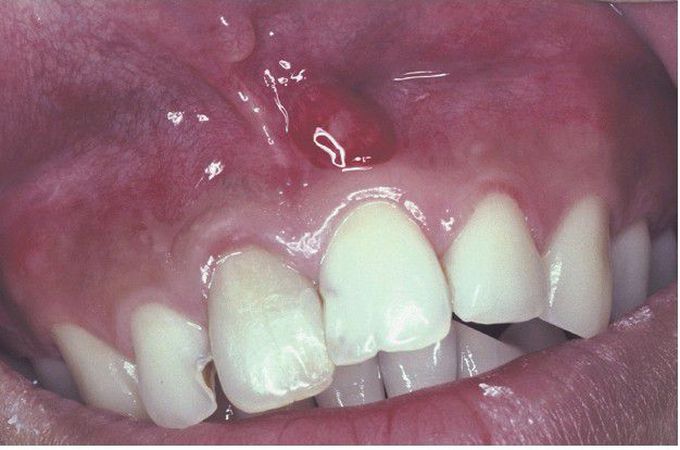

Parulis

. Erythematous mass of granulation tissue overlying the left maxillary central incisor. Note discoloration of the maxillary right central incisor.